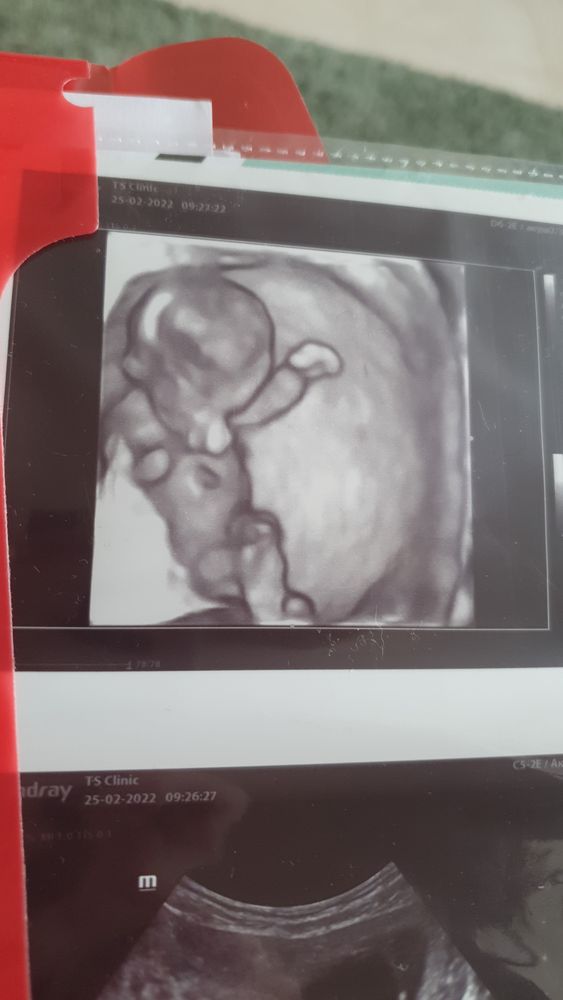

Изображение Вот такое мне сделали фото в 12 недель и сказали, что там вообще ничего не видно ,хоть так, хоть в 3д😁